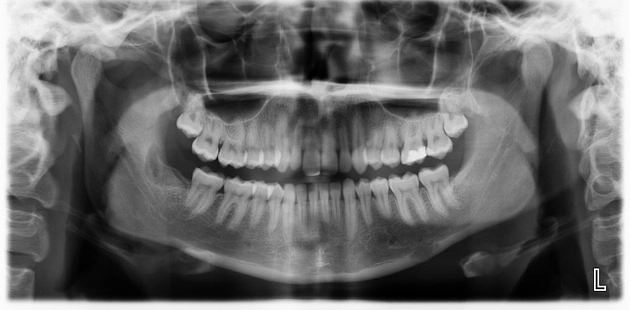

U răng (Odontoma)